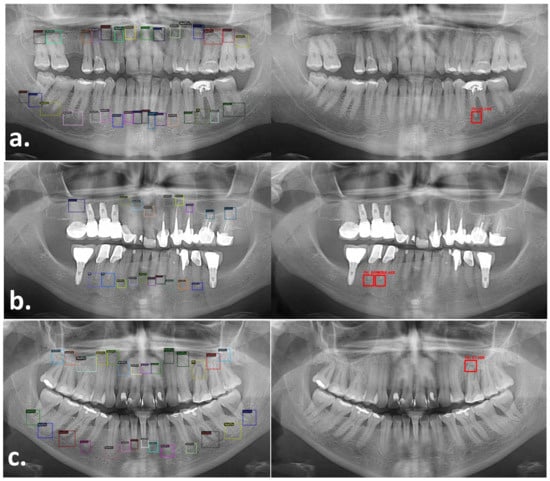

The detection and classification models were combined in order to produce our overall solution that was able to automatically identify the periapical lesions in the OPGs with red bounding boxes corresponding to Periapical Lesions. These boxes included a confidence score that represented a percentage calculated by the AI indicating how sure the AI was the output is correct. The overall solution was tested on a test set of 299 PL on 143 panoramic radiographs. The accuracy, sensitivity, and specify of the overall solution were 84.6%, 72.2%, and 85.6%, respectively. Figure 4 shows representative examples of the final output generated by the proposed method. This final tool was designed to detect periapical areas and ignore anything else in the radiograph, thus it was not affected by the presence of distractors and artifacts such as implants and crowns, also, the size of the detection box was able to adapt to the actual PRA, and it discriminated between different apices on the same tooth. On average, the proposed combined AI system took 2.3 s to detect and classify all PRAs as H or PL on a panoramic radiograph.

Figure 4. Performance of the proposed AI system for periapical lesion detection. This figure shows OPGs of three different cases (ac) labeled by the clinician (left) and the AI (right). For each row, the OPG on the left shows the boxes annotated by the expert including PL and healthy PRAs, while on the right, we show the same OPG labeled by the AI with red boxes indicating the PL detected by the AI. The confidence score calculated by the AI system can be found on top of each red boxes. Case “(a)” shows a periapical lesion detected in a multirooted tooth (#36). Case “(b)” shows two periapical lesions in teeth with root canal treatments and crowns in a patient with dental implants. Case “(c)” shows a case with a single PL in a multirooted tooth (#26).